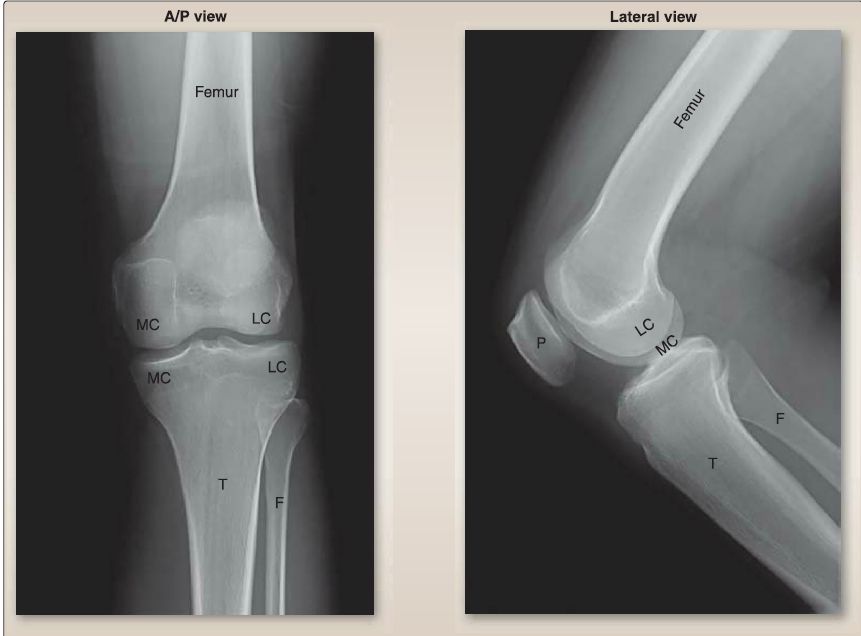

Figure 4: Plain film radiographs of normal knee joint. A/P = anterior/posterior, F = fibula, LC = lateral condyle, MC = medial condyle, P = patella, T = tibia.